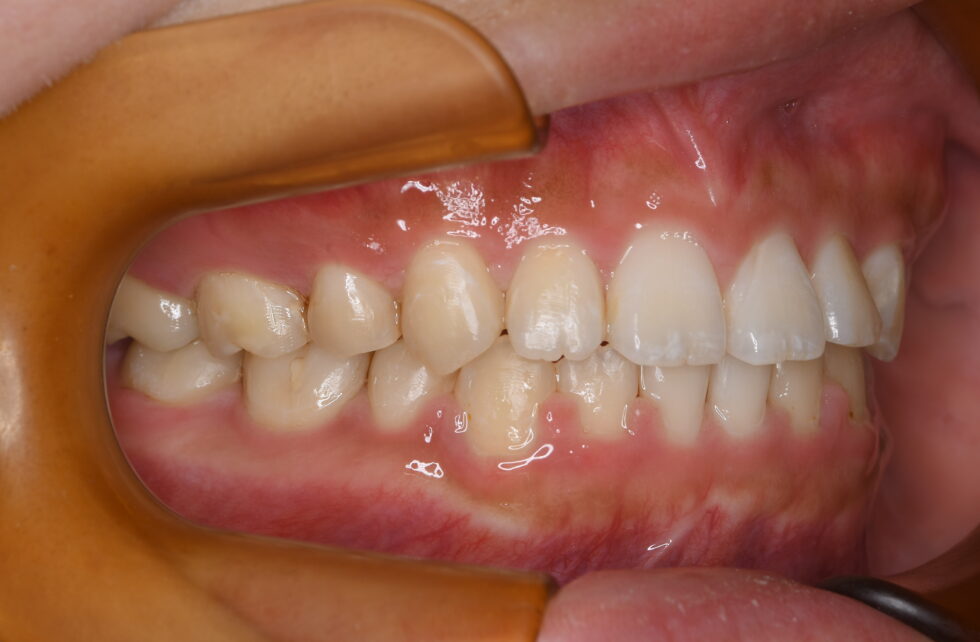

初診時年齢18歳の女性。叢生を伴う上下顎前突のケース

口元の突出および前歯の前傾を気にしておられました。審美的な矯正装置を希望されたため上顎舌側(裏側)・下顎唇側マルチブラケット装置を使用して、上下顎左右側小臼歯の抜歯による動的治療を行いました。前歯の前傾を改善し、口元の形態を整えることが出来ました。

動的治療期間は3年5ヶ月間